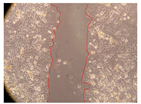

| 2 h | 8 h | 12 h | 24 h | |

| Control | ![]() | ![]() | ![]() | ![]() |

| P. viridis 250 mg/L | ![]() | ![]() | ![]() | ![]() |

| P. viridis 500 mg/L | ![]() | ![]() | ![]() | ![]() |

| B. caapi 250 mg/L | ![]() | ![]() | ![]() | ![]() |

| B. caapi 500 mg/L | ![]() | ![]() | ![]() | ![]() |

| M. hostilis 250 mg/L | ![]() | ![]() | ![]() | ![]() |

| M. hostilis 500 mg/L | ![]() | ![]() | ![]() | ![]() |

| Commercial mixture 250 mg/L | ![]() | ![]() | ![]() | ![]() |

| Commercial mixture 500 mg/L | ![]() | ![]() | ![]() | ![]() |

| P. viridis + B. caapi 250 mg/L | ![]() | ![]() | ![]() | ![]() |

| P. viridis + B. caapi 500 mg/L | ![]() | ![]() | ![]() | ![]() |

| P. viridis + P. harmala 250 mg/L | ![]() | ![]() | ![]() | ![]() |

| P. viridis + P. harmala 500 mg/L | ![]() | ![]() | ![]() | ![]() |

| M. hostilis + B. caapi 250 mg/L | ![]() | ![]() | ![]() | ![]() |

| M. hostilis + B. caapi 500 mg/L | ![]() | ![]() | ![]() | ![]() |

| M. hostilis + P. harmala 250 mg/L | ![]() | ![]() | ![]() | ![]() |

| M. hostilis + P. harmala 500 mg/L | ![]() | ![]() | ![]() | ![]() |

| Samples | 0 h | 2 h | p-Value | 8 h | p-Value | 12 h | p-Value | 24 h | p-Value |

|---|---|---|---|---|---|---|---|---|---|

| Control | 3.8 | 3.79 | - | 3.13 | - | 2.93 | - | 2.65 | - |

| P. viridis 250 mg/L | 2.36 | <0.001 | 2.06 | <0.001 | 1.5 | <0.001 | 0.53 | <0.001 | |

| P. viridis 500 mg/L | 2.97 | <0.001 | 2 | <0.001 | 1.64 | <0.001 | 0.54 | <0.001 | |

| B. caapi 250 mg/L | 3.23 | <0.001 | 1.71 | <0.001 | 1.42 | <0.001 | 0.75 | <0.001 | |

| B. caapi 500 mg/L | 3.08 | <0.001 | 2.24 | <0.001 | 1.42 | <0.001 | 1 | <0.001 | |

| M. hostilis 250 mg/L | 4.14 | <0.001 | 2.43 | <0.001 | 1.49 | <0.001 | 0.81 | <0.001 | |

| M. hostilis 500 mg/L | 2.43 | <0.001 | 2.07 | <0.001 | 1.76 | <0.001 | 0.4 | <0.001 | |

| Commercial mixture 250 mg/L | 3.79 | 1 | 2.05 | <0.001 | 1.39 | <0.001 | 0.49 | <0.001 | |

| Commercial mixture 500 mg/L | 3.14 | <0.001 | 1.85 | <0.001 | 1.11 | <0.001 | 0.69 | <0.001 | |

| P. viridis + B. caapi 250 mg/L | 2.10 | 0.001 | 1.38 | <0.001 | 1.23 | <0.001 | 0.25 | <0.001 | |

| P. viridis + B. caapi 500 mg/L | 2.73 | <0.001 | 1.5 | <0.001 | 1.29 | <0.001 | 0.63 | <0.001 | |

| P. viridis + P. harmala 250 mg/mL | 1.95 | <0.001 | 1.44 | <0.001 | 1.26 | <0.001 | 0.37 | <0.001 | |

| P. viridis + P. harmala 500 mg/L | 2.15 | <0.001 | 1.98 | <0.001 | 1.34 | <0.001 | 0.8 | <0.001 | |

| M. hostilis + B. caapi 250 mg/L | 2.08 | <0.001 | 1.65 | <0.001 | 1.38 | <0.001 | 0.47 | <0.001 | |

| M. hostilis + B. caapi 500 mg/L | 1.72 | <0.001 | 1.38 | <0.001 | 1.2 | <0.001 | 0.33 | <0.001 | |

| M. hostilis + P. harmala 250 mg/L | 2.83 | <0.001 | 1.71 | <0.001 | 1.07 | <0.001 | 0.3 | <0.001 | |

| M. hostilis + P. harmala 500 mg/L | 2.73 | <0.001 | 2 | <0.001 | 1.47 | <0.001 | 0.2 | <0.001 |